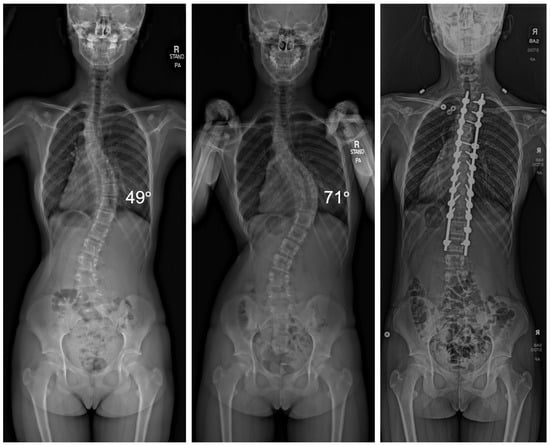

Among the 95 patients treated, there was an average curve progression of 5.2 degrees while awaiting surgery. This equated to an average of 1.91 degrees per month. A total of 48 patients of the 95 experienced curve progression of ≥5 degrees. Of the 91 patients that underwent VBT, 66 received thoracic tethers (72.5%), 12 received lumbar tethers (13.2%), and 13 received both thoracic and lumbar tethers (14.3%). Three patients required thoracic PSF, and one patient underwent both thoracic and lumbar PSF (Figure 1).

Figure 1.

Radiographic imaging of a patient before and after a 6-month surgical delay that resulted in curve progression from 49° to 71°, requiring the transition from VBT to PSF.

Patients with VBT with thoracic tethers had an average progression of 4.5 degrees (range: −7 degrees to 32 degrees), while patients with lumbar tethers had an average progression of 2.8 degrees (range: −6 degrees to 12 degrees). Patients with both thoracic and lumbar tethers had an average thoracic progression of 6.2 degrees (range: 2 degrees to 22 degrees) and an average lumbar progression of 5.2 degrees (range: −1 degrees to 21 degrees). Patients that required PSF had an average thoracic progression of 14 degrees (range: 6 degrees to 21 degrees). The single patient with a lumbar curve had a progression of 13 degrees.